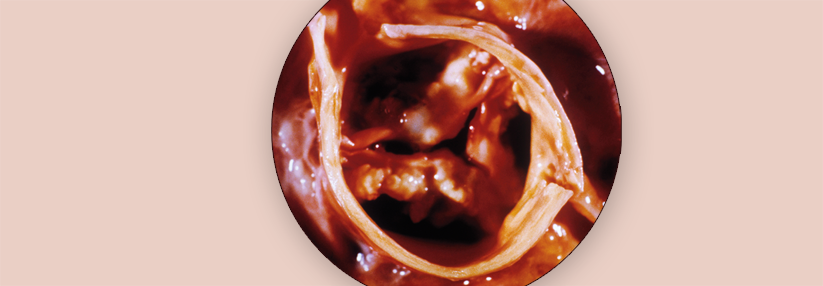

Es gibt verschiedene Formen bzw. Ursachen der Aortenklappenstenose:

• Kongenitale Form, die oft bei Jugendlichen und jungen Erwachsenen diagnostiziert wird und häufig mit Klappenauffälligkeiten einhergeht (z.B. unikuspide oder bikuspide Aortenklappe)

• Degenerativ-kalzifizierte Form, bei über 70-Jährigen die häufigste Ätiologie

• Rheumatische Aortenstenose (in Ländern mit modernen Gesundheitssystemen selten geworden, da das rheumatische Fieber aufgrund konsequenter Antibiose kaum noch beobachtet wird)